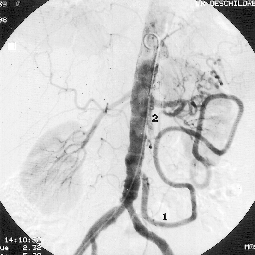

Vorgestellt Ischemie Mesenterique

Très courte, première branche majeure de l' aorte abdominale (les suivantes étant les artères mésentériques supérieure puis inférieure ). Il approvisionne en sang oxygéné le foie, l' estomac, la rate, le duodénum et le pancréas. Mais surtout, dans 23% des cas, elle participe à la vascularisation du foie, habituellement comme rameau accessoire, mais parfois, dans 6% des cas, en remplacement de la branche droite ou de la branche … Autour de l origine du tronc coeliaque et de l artère mésentérique supérieure. Le tronc cœliaque est une artère ;Autour de l origine du tronc coeliaque et de l artère mésentérique supérieure.